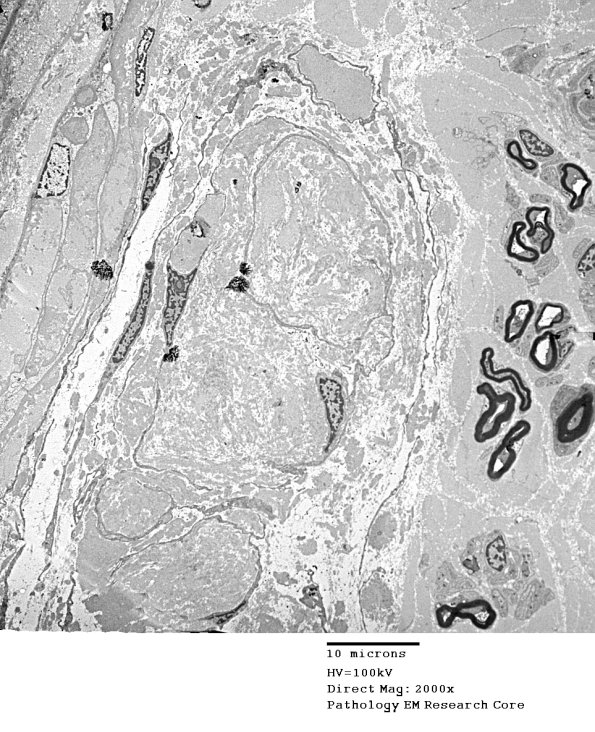

A low magnification electron micrograph of the RB shown in #1A2. This RB is rich in dense connective tissues as shown in the following images. (electron micrograph)